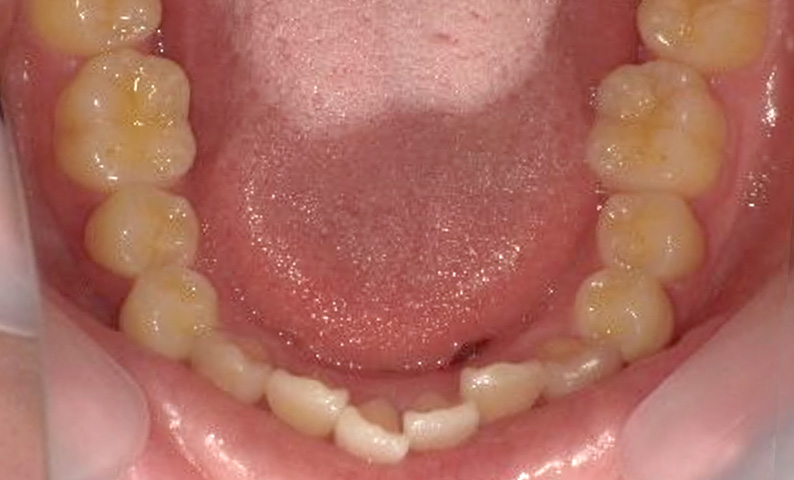

症例_002 上下顎の部分矯正

治療期間:7ヶ月金額:54万円+税女性前歯のガタガタ出っ歯八重歯

| Before | After |

|---|---|

|